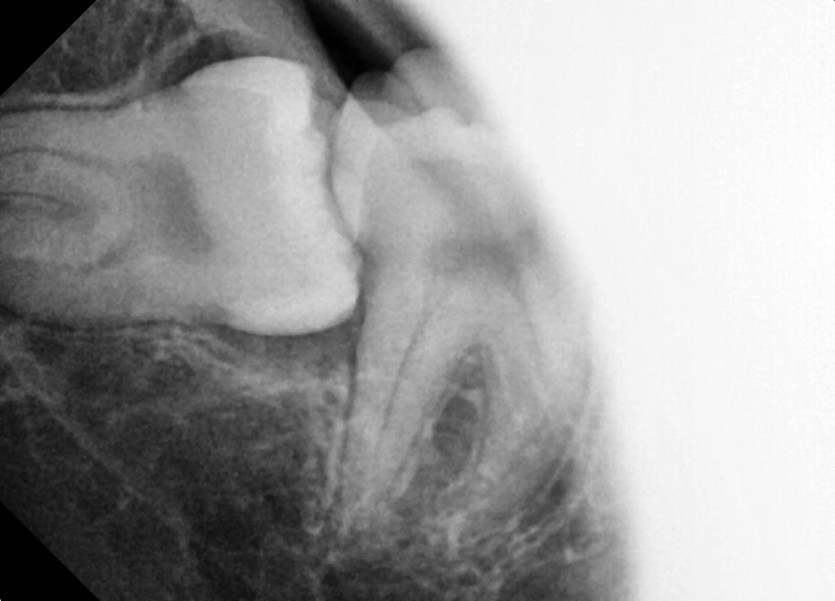

#48 사랑니 발치

구강 외과 전문의가 당일 발치했습니다.